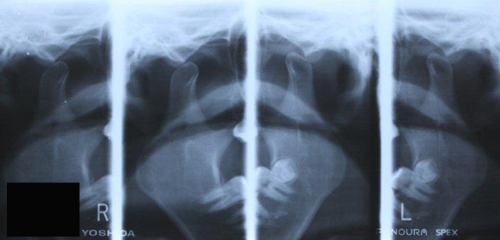

顎関節脱臼

顎関節脱臼とは、顎関節すなわち顎の関節の脱臼のことを言います。

顎関節を構成する下顎骨と側頭骨の位置が正常なところからずれてしまい、顎の運動に機能的な障害が起こった状態になり、「顎が外れた」と表現されることが多いのが、この顎関節脱臼の症状です。